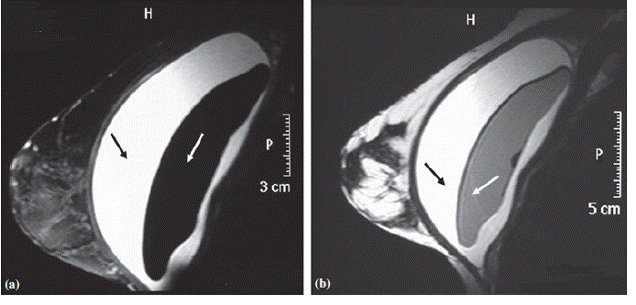

Медицинские исследования: МРТ молочных желез с имплантами